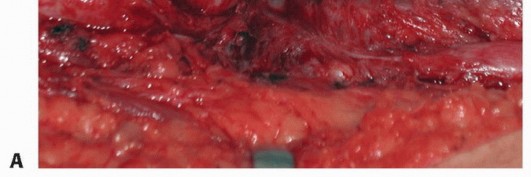

Internal neurolysis is defined as the resection of fibrotic tissue from within the structure of the nerve itself. This procedure is indicated for late management of incomplete injuries such as stretch injuries when the nerve has regained partial function that is clinically inadequate. Intraoperative recording of NAPs will indicate functioning fascicular groups and help guide the surgeon during this procedure. Internal neurolysis is performed along the fascicular segment that has lost NAPs (TECH FIG 2). This procedure is performed in cases of incomplete functional loss distal to the site of injury. Some loss of intact axons can be expected as a result of the dissection, so the patient should be advised that additional loss of function could be possible with this procedure.

P.838

TECH FIG 2 •A-C.Intraoperative microscope images of internal neurolysis of the ulnar nerve at the wrist.A.The ulnar nerve is surrounded by dense scar tissue.B.After external neurolysis, there is a persistent area of narrowing of the nerve (arrows) requiring internal neurolysis.C.Appearance after internal neurolysis—the constricting epineurium and scar between fascicles has been excised.D.Illustration of a neuroma in continuity treated by internal neurolysis. The segment of scarred epineurium is excised, and all scar tissue between fascicles also is excised.